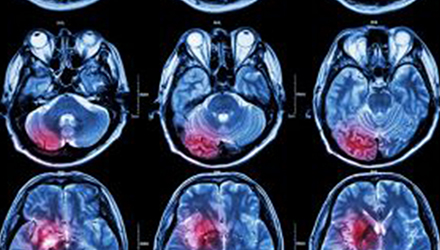

在這項研究中,研究人員使用功能核磁共振成像(fMRI)觀察大腦中血液含氧量的變化。研究人員首先研究了耳鳴患者和無耳鳴者的大腦活動,其目的是比較兩組受試者大腦處理情緒的方式。

在功能磁共振成像檢查中,受試者分別聽30種“愉悅”的聲音、30種“不愉快”的聲音和30種“中性”的聲音。這些聲音包括小孩咯咯笑,嬰兒啼哭,以及熱水壺燒開的聲音。

功能磁共振成像的結果顯示,當暴露于情緒性聲音下,耳鳴患者大腦不同區域的活動比沒有耳鳴者的活動更強烈。接著,研究人員進行了更深入的研究:耳鳴患者的大腦活躍性和耳鳴嚴重程度的關系。